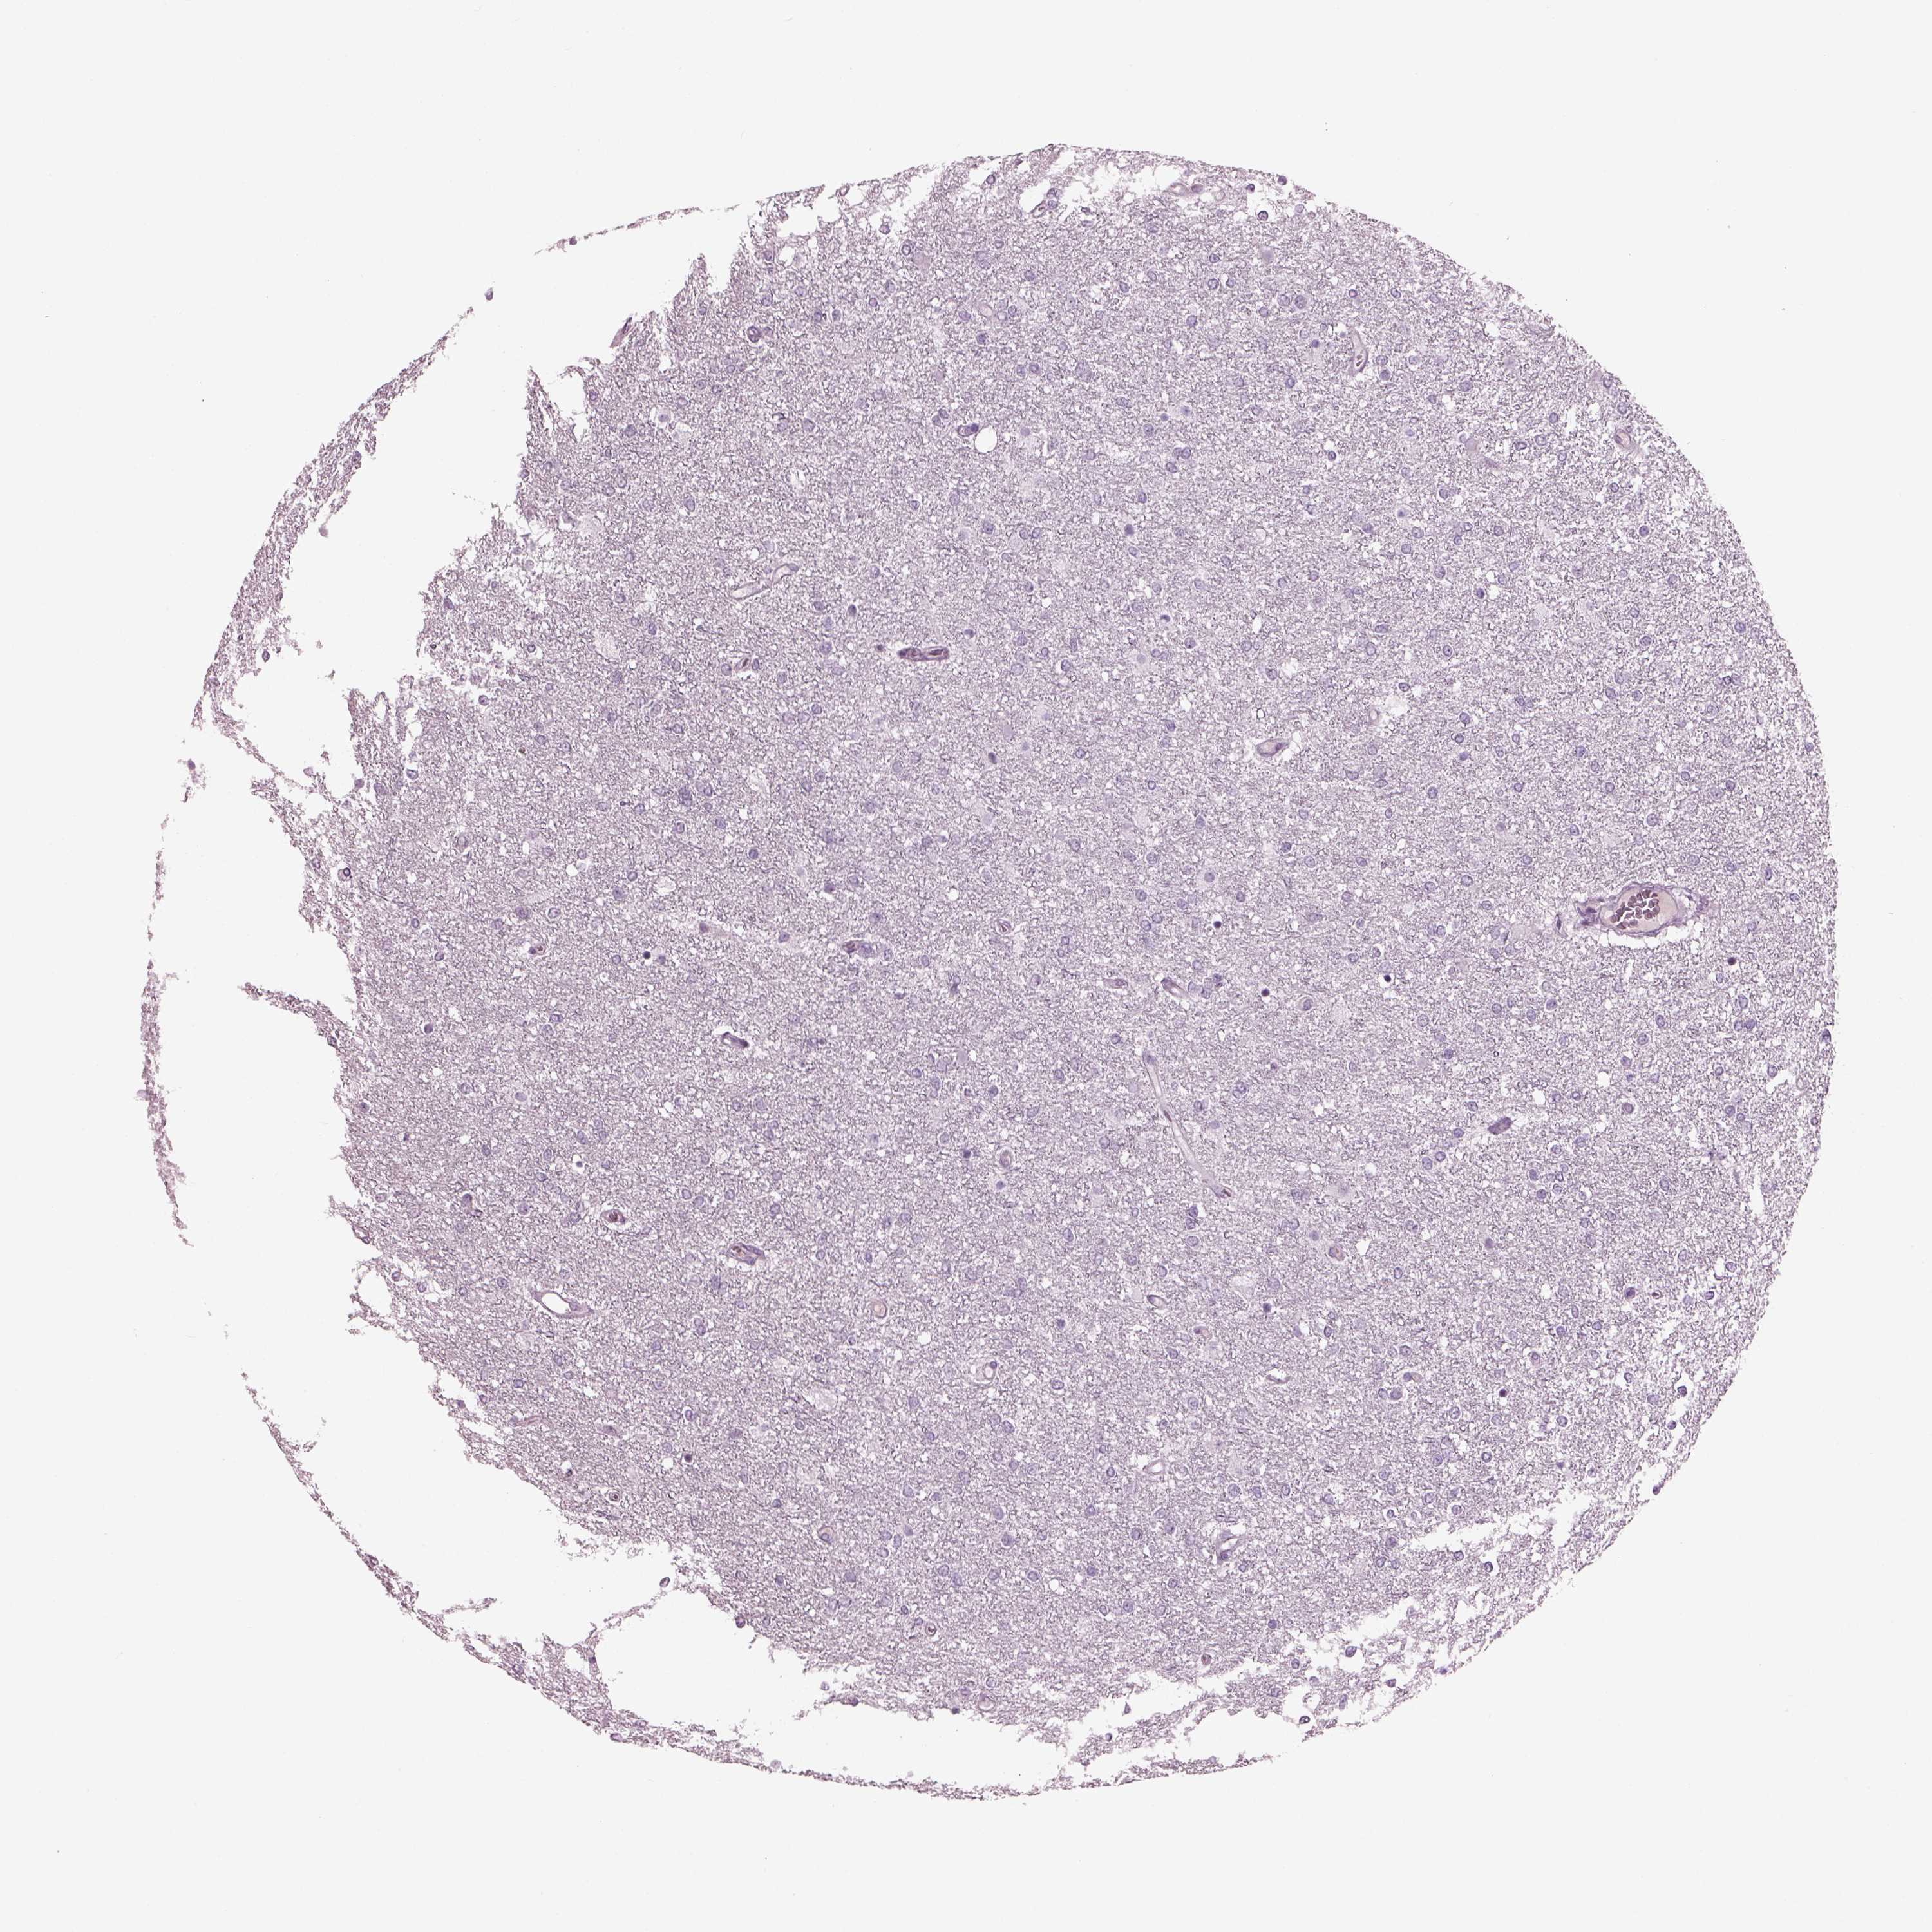

GLIOMA - Protein expressioni

A mouse-over function shows sample information and annotation data. Click on an image to view it in a full screen mode. Samples can be filtered based on level of antibody staining by selecting one or several of the following categories: high, medium, low and not detected. The assay and annotation is described here.

Antibody stainingi

Antibody staining in the annotated cell types in the current human tissue is reported as not detected, low, medium, or high, based on conventional immunohistochemistry profiling in selected tissues. This score is based on the combination of the staining intensity and fraction of stained cells.

Each image is clickable and will lead to virtual microscopy that enables deeper exploration of all samples and also displays staining intensity scores, fraction scores and subcellular localization as well as patient and tissue information for each sample.

Antibody HPA070355

Antibody HPA078303

Staining

High

Medium

Low

Not detected

Intensity

Strong

Moderate

Weak

Negative

Quantity

>75%

75%-25%

<25%

None

Location

Nuclear

Cytoplasmic/membranous

Cytoplasmic/membranous,nuclear

Glioma, malignant, Low grade

Glioma, malignant, High grade